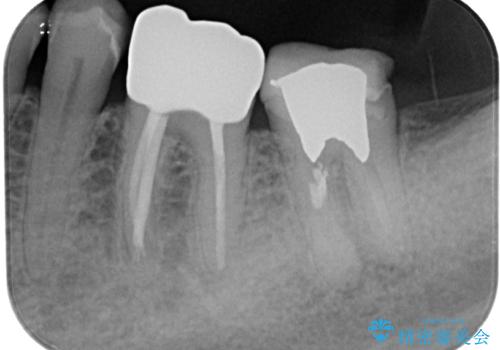

下顎大臼歯の再根管治療とオールセラミッククラウンによる補綴治療

- 左下の奥歯の被せものが外れ、噛むと痛みがあると来院された患者様です。

歯根破折の疑いがあり、顕微鏡下で染色して確認したところ破折線は認められませんでした。

そのため再根管治療の適応と判断し、治療を進めていくこととしました。